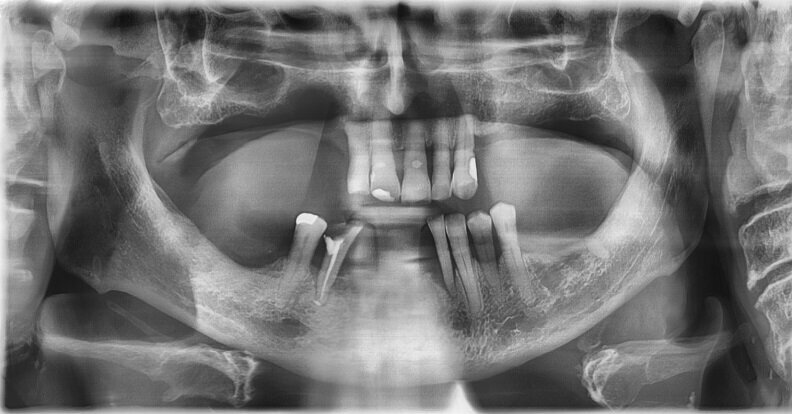

Ryc. 1-3_Stan przed leczeniem: 2. Zdjęcie rtg okołowierzchołkowe

Kontrola została wykonana po 2 i 12 tygodniach po zabiegu. W tym czasie zaobserwowano gojenie się tkanek miękkich. Po 12 tygodniach wykonano badanie radiologiczne, które nie wykazało objawów zmniejszenia grubości blaszki kostnej, co mogłoby świadczyć o przewlekłym stanie zapalnym.